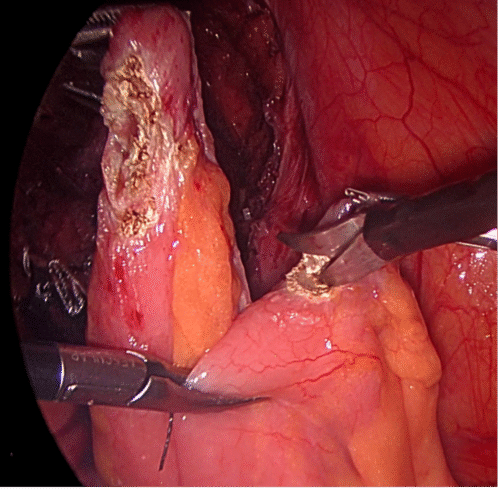

Debido a lo primitivo de los registros y comunicaciones de la época, la paternidad de la primera nefrectomía radical es controvertida. Las búsquedas muestran que la primera nefrectomía exitosa la realizó el cirujano alemán Gustav Simon en la Universidad de Heidelberg el año 1869. También hay testimonios que indican que el Dr. William Hingston, cirujano canadiense, en 1868 en el Hotel Dieu Hospital en Montreal, habría efectuado también una exitosa nefrectomía(16). Lo que sí está meridianamente claro es que 122 años después, en 1990, el Dr. Ralph Clayman en la Universidad de Washington (St. Louis), realizó la primera nefrectomía radical laparoscópica, la cual se transformó en la técnica estándar para la nefrectomía radical por cáncer(17,18). Esta cirugía puede efectuarse tanto por un acceso transperitoneal como retroperitoneal, dependiendo de las preferencias del cirujano o de las características particulares del paciente o tamaño del tumor. Cuando se realizan por el acceso transperitoneal, debe movilizarse ampliamente el colon derecho o izquierdo (incluyendo ángulos hepáticos y esplénicos), según corresponda, para extirpar en bloque la bolsa de Gerota y su contenido (Figura 20). En el lado derecho hay que hacer necesariamente una maniobra de Kocher (movilizar el duodeno) para acceder con comodidad al hilio renal (Figura 21).

Una manera segura y sencilla de acceder al hilio renal es disecar la Gerota en su extremo caudal, separándola de su íntima unión con el músculo psoas lumbar. Una vez ubicado el hilio, este debe ser disecado para controlar por separado arteria y vena. Usamos clips de ligadura de polímeros en forma rutinaria (ejemplos: Hem-o-LockTM, Teleflex), dos proximales y uno distal (Figura 22).